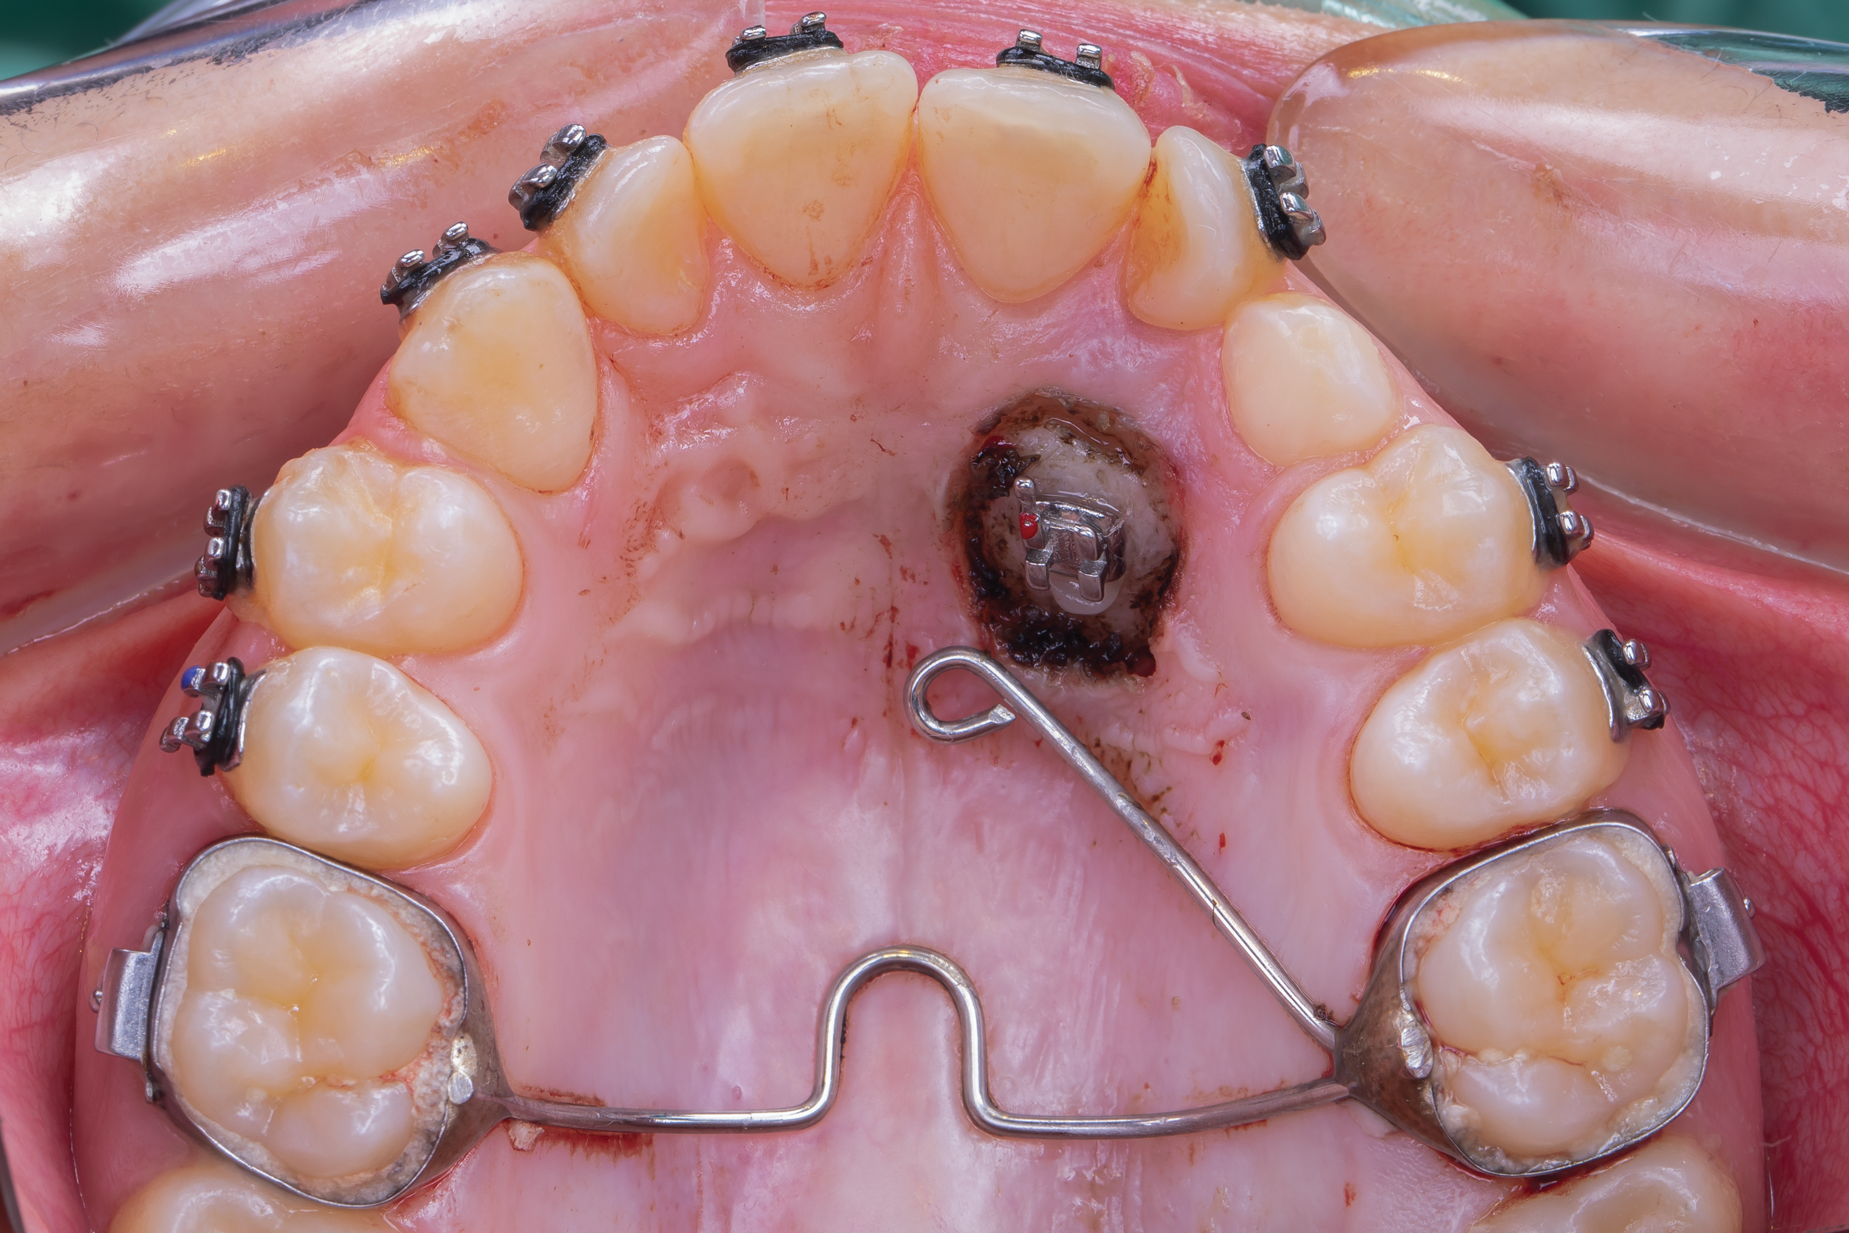

Open exposure-A semilunar internal bevel incision is made with a 15 or 15c blade along the mesio-palatal portion of the tooth, continuing to the disto-palatal area. A bevel incision should be performed toward the bone.49 A full-thickness flap is elevated with periosteal elevators. The removal of the bony crypt is completed with curettes and rotary instruments. The follicle is carefully removed with curettes, and the canine is exposed.45 The bony crypt is sufficiently exposed to permit proper positioning of the bracket. The bracket is placed, and a wire is tied to it. Bleeding in the area is controlled with the use of local anesthesia, bone wax, or gauze impregnated with 1:50,000 anesthesia.45 A new 15c blade is used to fenestrate the gingival tissue at the bracket location and create a trap door exposing the bracket through the flap, which is secured with sutures.49 The use of a periodontal dressing in the area is optional.8,45,48,49 Orthodontic forces are applied 2 weeks later in cases where direct traction is desired.27 It has been suggested to allow spontaneous eruption to the occlusal plane after the open exposure, and then direct the canine bucally (Figure 8 and Figure 9).9,26,27

Fig 8. Open exposure (Fig 8) with spontaneous eruption for 7 months. Once the canines reached the occlusal plane, buccal traction was performed for an additional 5 months. Total treatment time to move the bilateral palatal impacted canines into the arch was 12 months (Fig 9).

Fig 9. Open exposure (Fig 8) with spontaneous eruption for 7 months. Once the canines reached the occlusal plane, buccal traction was performed for an additional 5 months. Total treatment time to move the bilateral palatal impacted canines into the arch was 12 months (Fig 9).